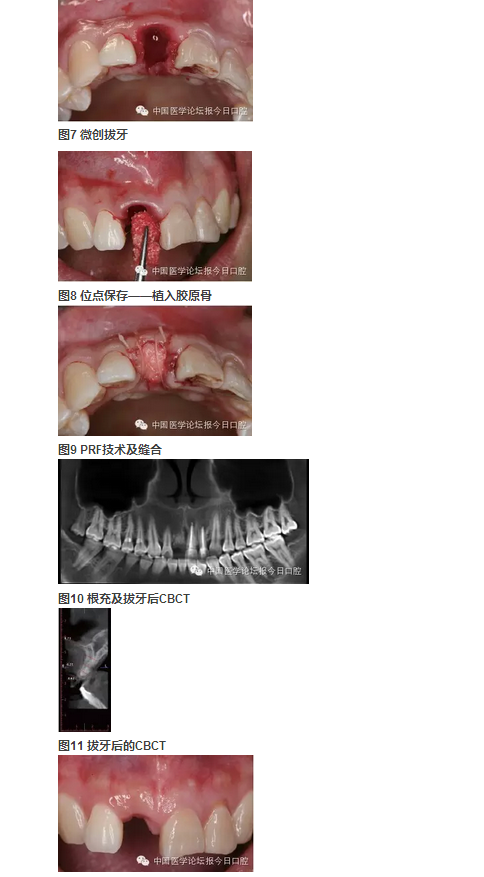

4.右上中切牙牙槽窩位點保存+富血小板纖維蛋白(PRF)技術。

②右上中切牙牙槽窩位點保存+PRF技術治療,避免了牙槽嵴可能發(fā)生的三維方向骨缺損,極大限度保持和原位重建局部骨量;

③符合PRF技術的牙槽窩位點保存技術,充分應用了PRF技術在軟組織愈合上的優(yōu)勢。經(jīng)PRF膜技術在封閉牙槽窩的同時,促進牙齦上皮的生長。在局部軟組織愈合的條件下,進一步促進骨組織的生長。從而最大限度地保存了種植位點的骨量。

位點保存技術包含軟組織與硬組織的保存。通常牙缺失后牙槽嵴在1個月之內(nèi)軟組織修復重建,而硬組織尚未明顯吸收。但這個時期如不給予人為干預,軟組織修復常陷于牙槽窩內(nèi),形成凹陷,不利于植入種植體后的軟組織成形及傷口的關閉。

國際口腔種植學會前任主席Buser介紹的完整的位點保存技術是:拔牙后植入膠原骨,1個月以后軟組織重建修復形成較為豐滿的外形,然后再切開,將牙槽窩內(nèi)殘存的膠原骨刮除,植入骨粉3~6個月后再行種植體植入,這樣確保了拔牙位點豐滿的外形。

軟硬組織修復重建分兩步進行的原因是:膠原骨有較好的細胞趨化特性,可促進鄰近的牙齦組織生長進入,但膠原骨會較快吸收,在其完成誘導軟組織生長任務后,更換為吸收速率較低的充填材料(Bio-Oss小牛無機骨粉)更利于硬組織的修復重建及重建后穩(wěn)定性;如直接選用吸收速率較低的充填材料一次完成位點保存,由于軟組織量不足,在牙槽嵴頂部常難維持骨粉的位置。

該病例屬于軟組織的位點保存,可看到,二期手術時,軟組織已較豐富,但翻開后可見硬組織,既無明顯的重建也無明顯的吸收,在植入種植體后,可將傷口理想地關閉。